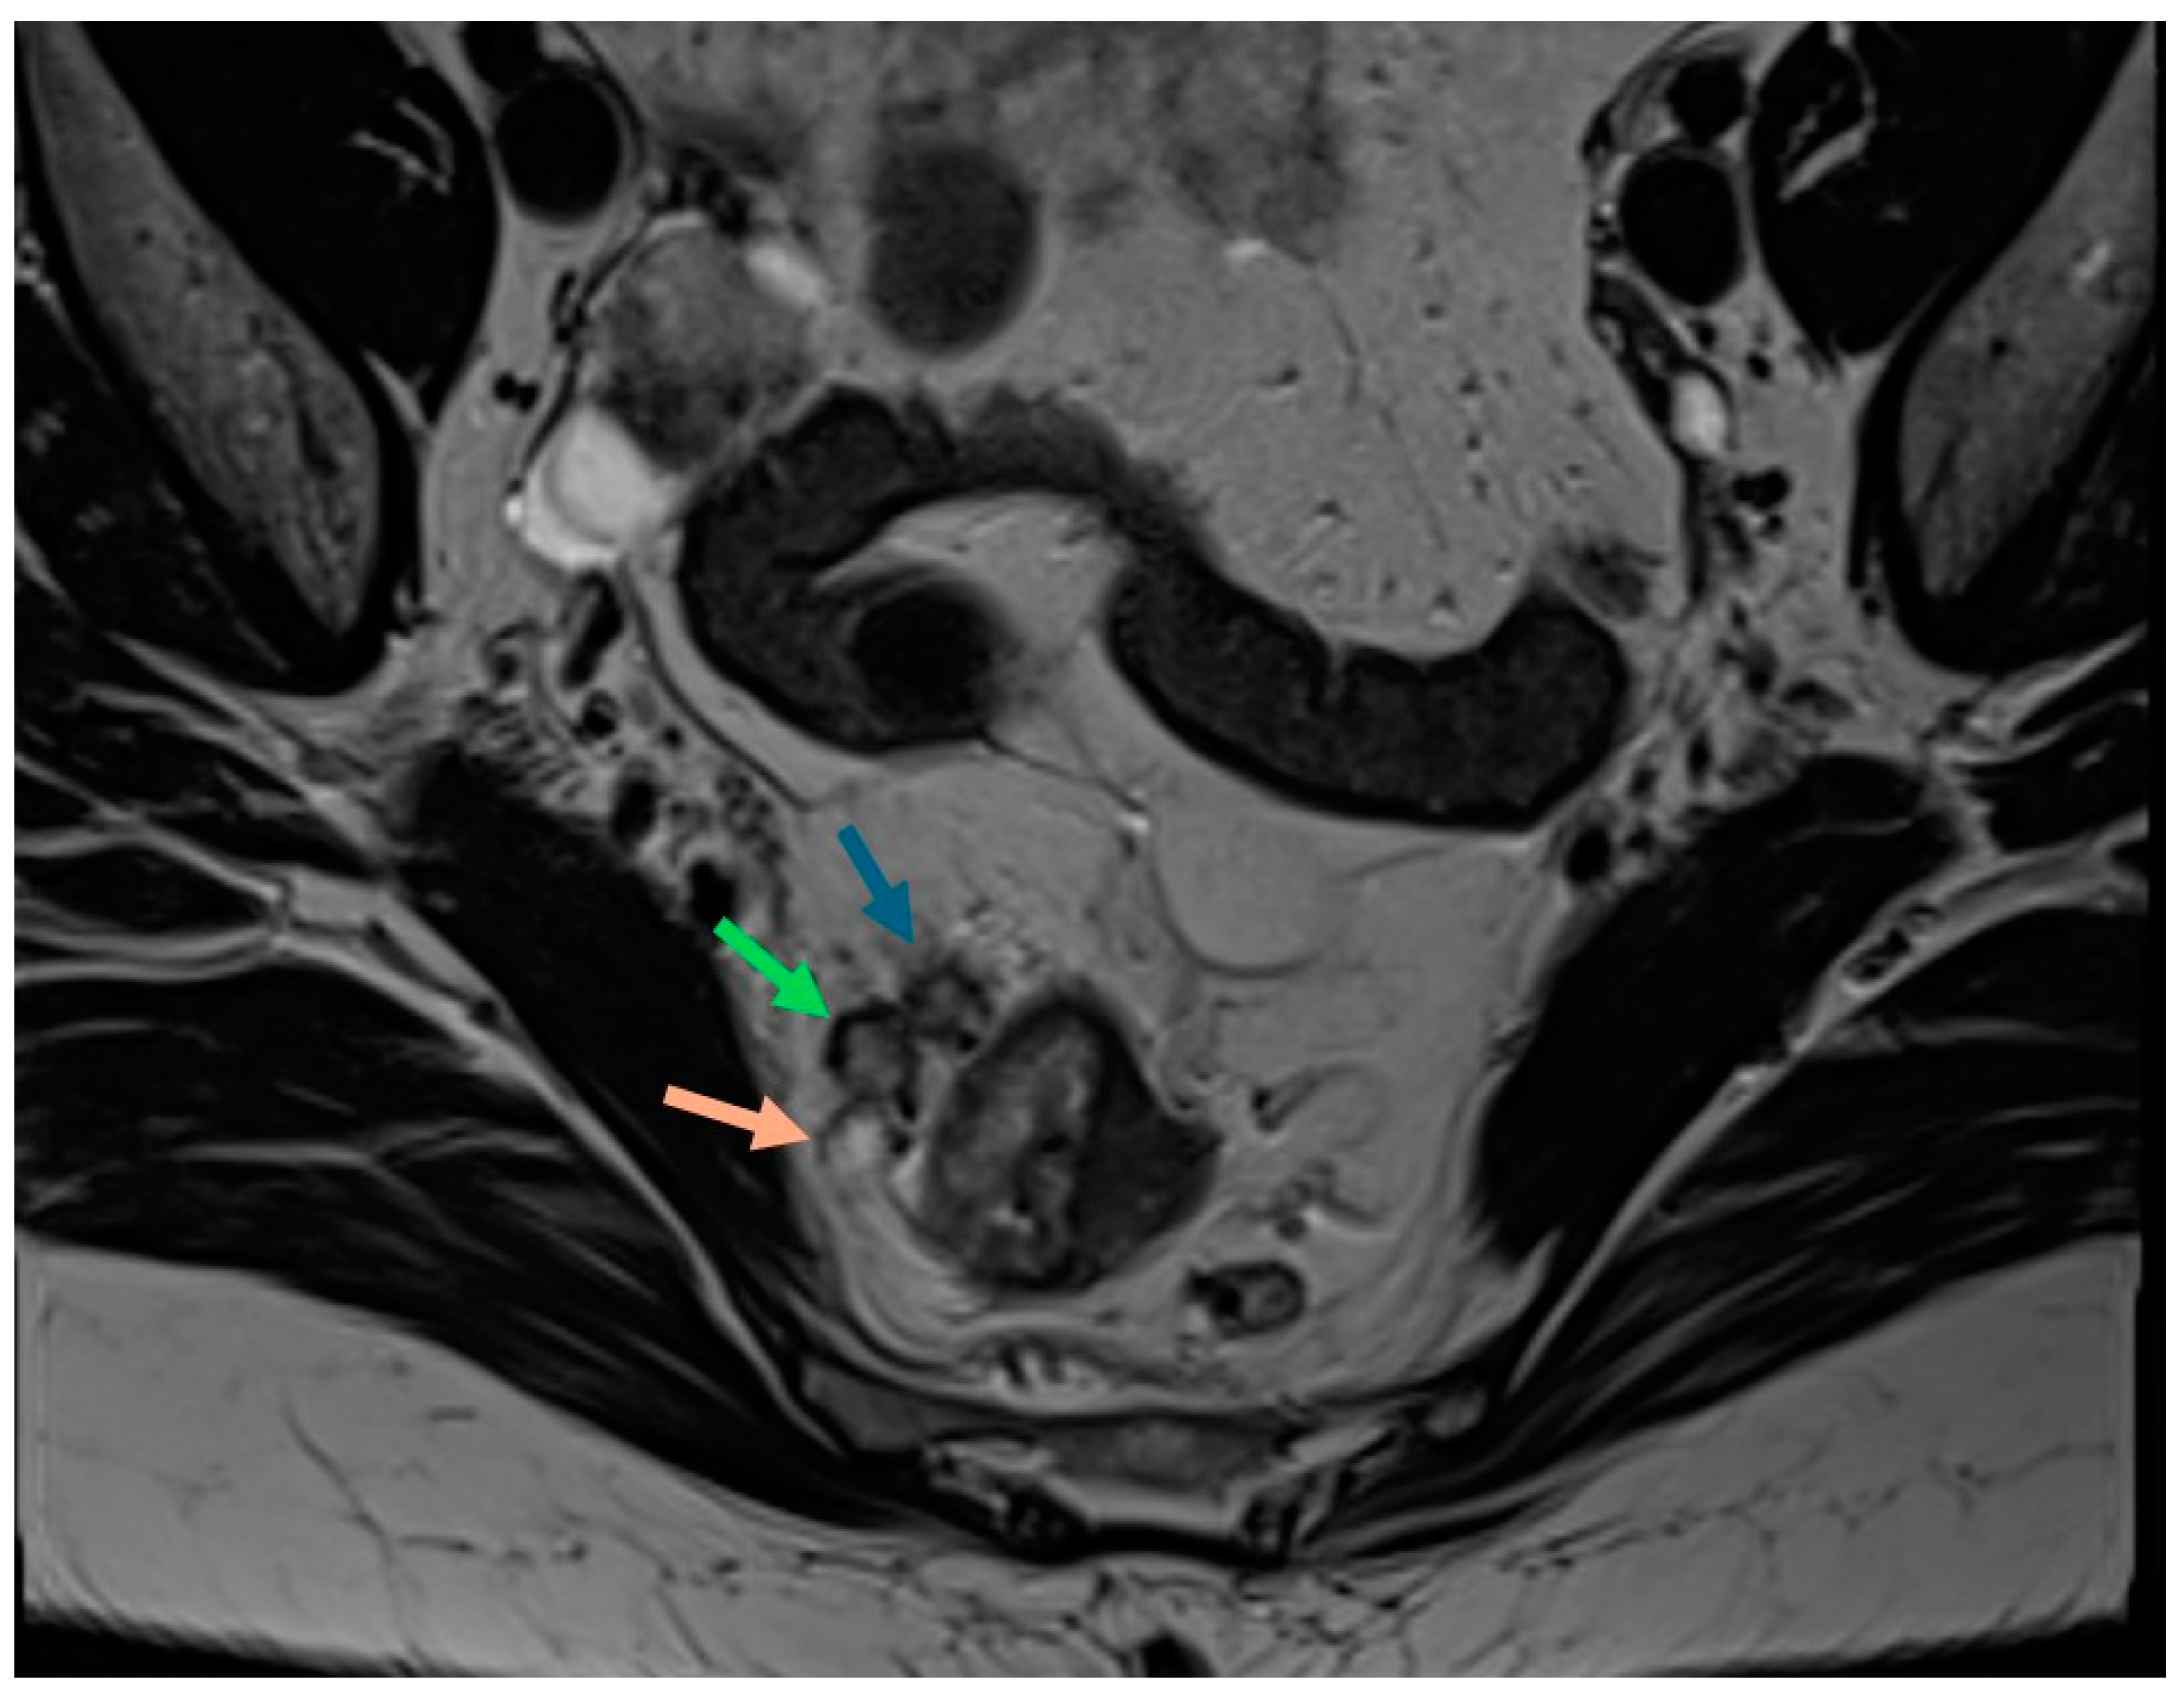

2.5. Lymph Nodes

| Lymph nodes | Malignant lymph nodes criteria: short axis diameter ≥9 mm, 5–8 mm and ≥2 suspicious features, <5 mm and 3 suspicious features, all mucinous lymph nodes; morphologically suspicious features: round shape, irregular border, internal heterogenous signal; |

| Tumour deposits (N1c) | Tumour deposits follow the course of a venous channel compared to lymph nodes which are usually isolated within the mesorectal fat |